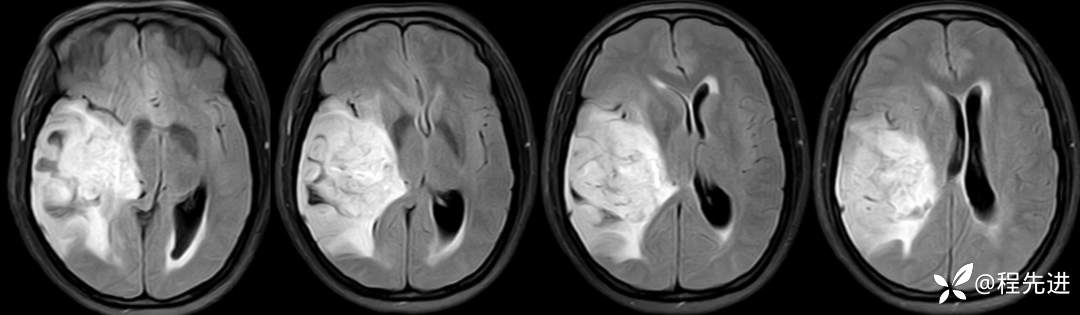

FLAIR: